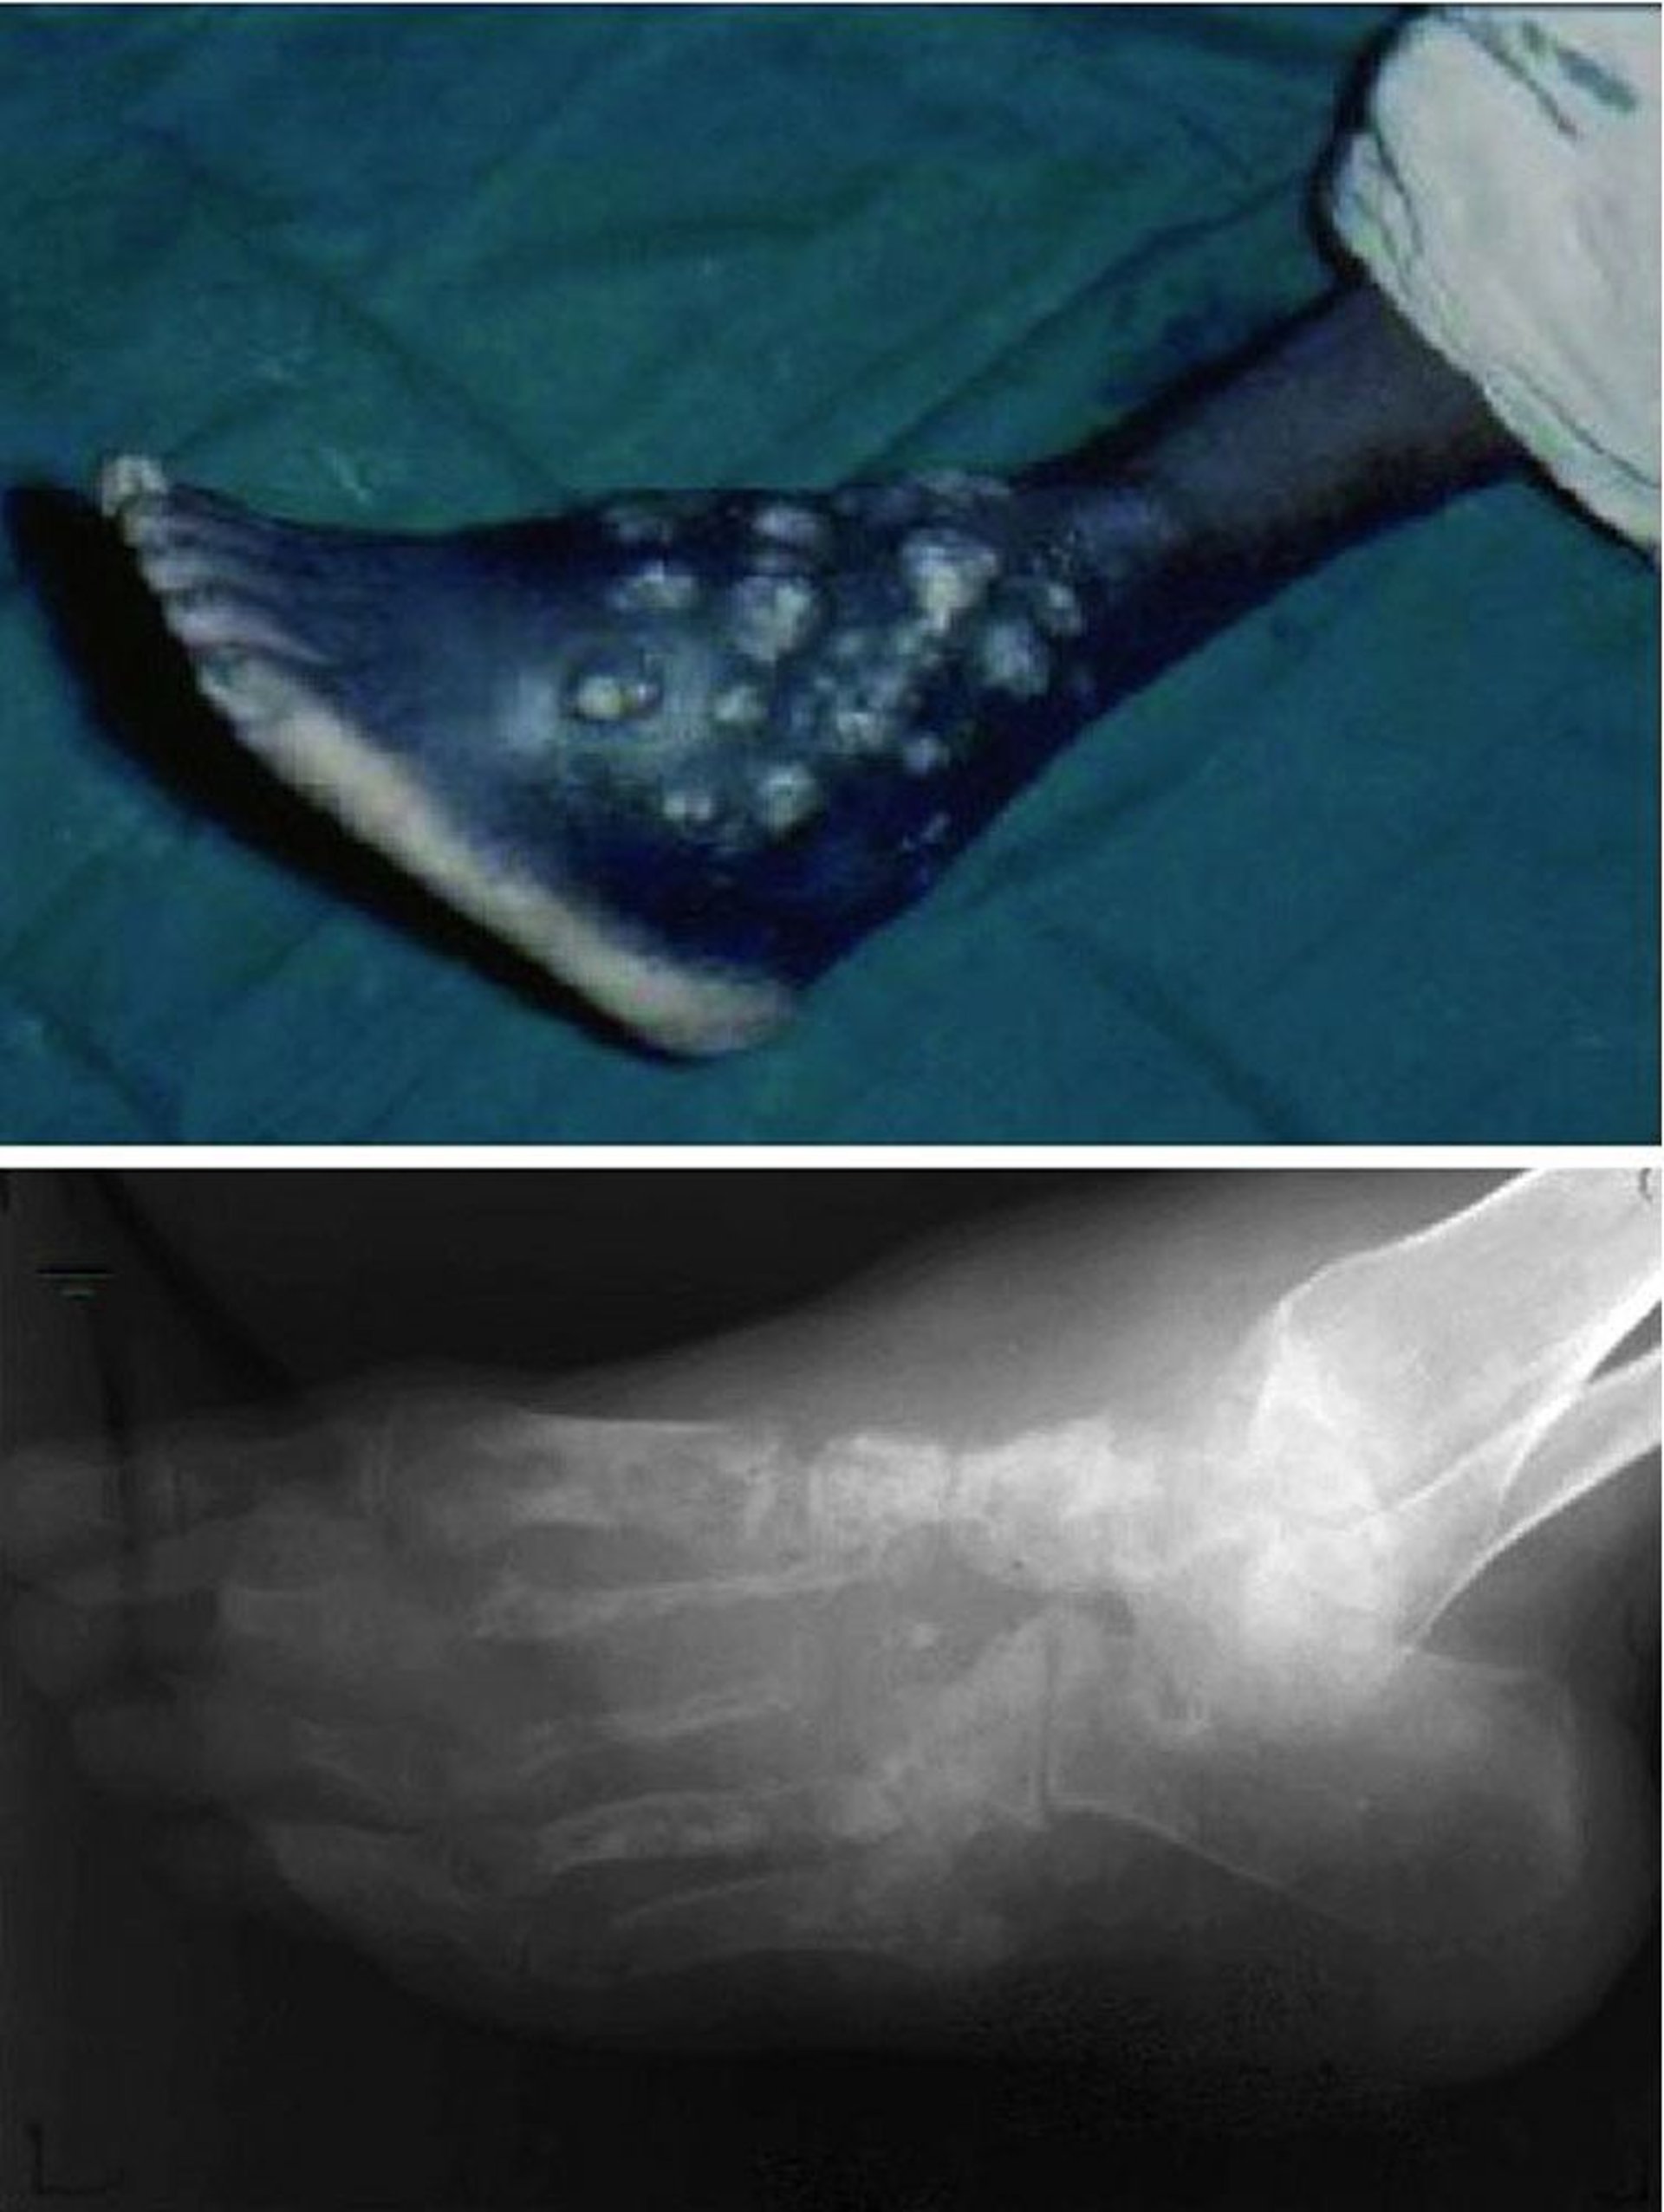

Мицетома (мадурская стопа)

На этой фотографии показаны хронические незаживающие раны с рецидивирующими эпизодами гнойных выделений и изъязвлений (вверху) и прогрессирующим разрушением костной архитектуры всей стопы (внизу).